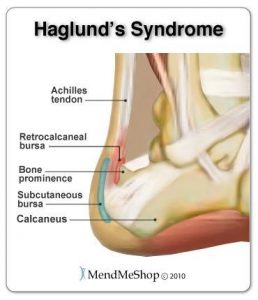

Il morbo o sindrome di Haglund prende il nome dal medico che per primo la descrisse nel 1028. Si tratta di un’infiammazione di una porzione del calcagno, che evolve come una sporgenza dolorosa accompagnata da ipercheratosi (ispessimento tissutale) subito sotto il tendine d’Achille.

La malattia di Haglund si sviluppa lentamente nel corso degli anni e si manifesta con dolore e difficoltà motorie in età adulta. Si manifesta con una protuberanza ossea che si forma sulla parte posteriore del calcagno e provoca l’infiammazione delle borse sierose che proteggono il tendine d’Achille dallo sfregamento osseo. Nei casi in cui la malattia non venga curata in tempo, si creano delle callosità attorno la protuberanza, che spesso entra in conflitto con le calzature provocando lesioni e ferite della cute. Colpisce più frequentemente donne e sportivi, a causa del tipo di calzature indossate e dello sforzo a cui viene sottoposto il tallone. Corridori, maratoneti e marciatori sono gli sportivi più soggetti allo sviluppo del morbo di Haglund. Le cause del morbo di Haglund possono anche essere di tipo genetico, ma sono meno frequenti di quelle funzionali.

I sintomi del morbo di Haglund sono essenzialmente il dolore provocato dall’infiammazione dei tessuti e del tendine e quello provocato dallo sfregamento della protuberanza con le calzature. Borsite, ipercheratosi e calli si possono presentare frequentemente.

Il dolore può estendersi anche lungo il tendine di Achille, e nei casi più gravi risalire anche verso il tricipite surale. Altro sintomo è la presenza più o meno vistosa di una sporgenza ossea.

Il dolore dietro il tallone chiamato Morbo di Haglund è una patologia molto frequente, che per definizione è dovuto alla crescita anomala di una esostosi dietro il calcagno, proprio in corrispondenza dell’inserzione del tendine d’Achille sul Calcagno del piede.